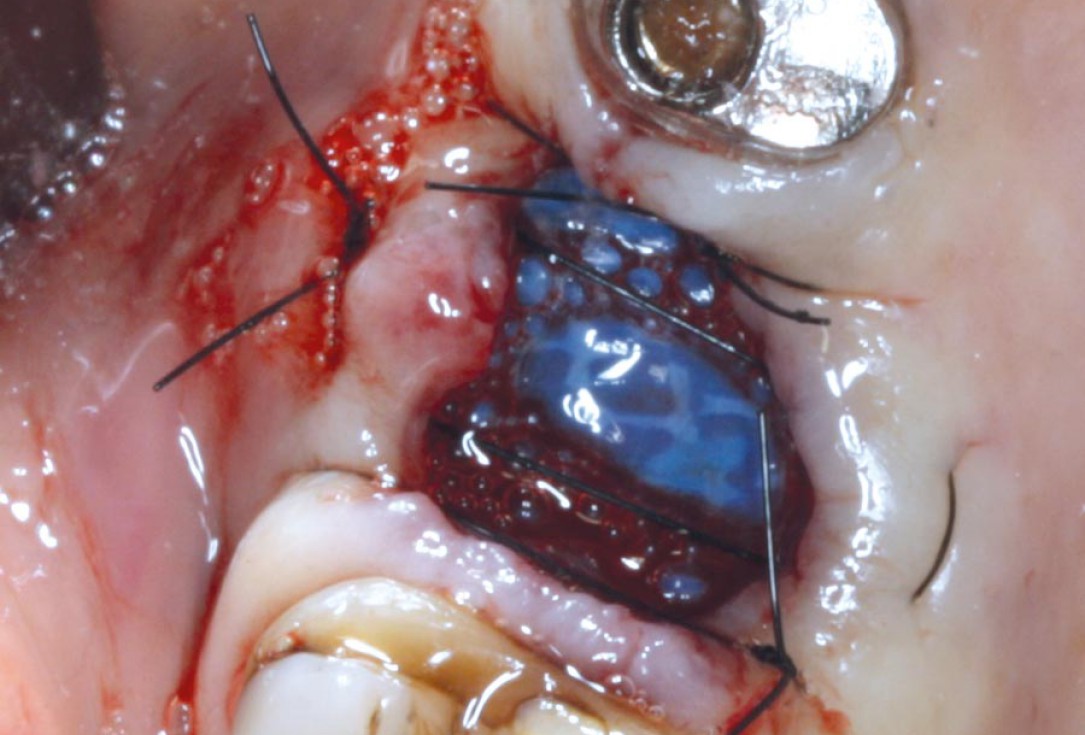

04/07 - Extraction socket covered with permamem®. The membrane is placed under the soft tissue.Socket preservation with permamem® - Dr. M. Turco

05/07 - Stabilization of the extraction site and immobilization of the membrane with cross sutures.Socket preservation with permamem® - Dr. M. Turco